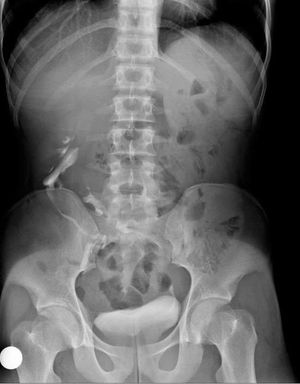

Epidemiology The estimated incidence is around 1 out of 1000 births 1. There is a recognised male predilection with a 2:1 male to female ratio. More than 90% of crossed renal ectopia results in fusion. Pathology It results as a consequence of abnormal renal ascent in embryogenesis with fusion of the kidneys within the pelvis. It is thought to occur in the first trimester, at around 4th-8thweek of fetal life (In a normal situation the kidney reaches its appropriate position at L2 level at the end of the 2nd month). Some evidence supports that an abnormally situated umbilical artery prevents normal cephalic migration. Another theory is that the ureteric bud crosses to the opposite side and induces nephron formation in the contralateral metanephric blastema. The result is a single renal mass with two collecting systems being located on one side of the abdomen. Normal ascent of the kidneys is required for formation of the extraperitoneal peri-renal fascial planes and therefore ectopia (or renal agenesis) results in failure of development of fascial layers in the flanks on the side not occupied by renal tissue. The lack of restraining fascia leads to possible malposition of bowel into the extra-peritoneal fat of the empty renal fossa and relaxation of mesenteric supports for bowel loops in this region. Subtypes type a: inferior crossed fusion type b: sigmoid kidney type c: lump kidney type d: disc kidney type e: L-shaped kidney type f: superiorly crossed fused Location Left-to-right ectopy is thought to be three times more common. Radiographic features Fluoroscopy Urography (IVU) The anomaly is readily detected on conventional urography. In 90% of crossed ectopy, there is at least partial fusion of the kidneys (the remainder demonstrate two discrete kidneys on the same side, crossed-unfused ectopy). An anterograde or retrograde ureterogram most often demonstrates normal bladder trigone without ureteral ectopy. Barium studies of the bowel Barium contrast studies of the bowel should be interpreted in light of bowel laxity in the region of the empty renal fossa (discussed above). In particular, distinction must be made from internal hernia. Ultrasound On ultrasound there may be a characteristic anterior or posterior "notch" between the two fused kidneys. CT The parenchymal band joining the two kidneys can be better visualized on CT scan. Also, anatomical relationship with adjacent structures and positions of the ureter can be better assessed. Complications In a crossed fused renal ectopic kidney, complications such as nephrolithiasis, infection, and hydronephrosis approaches ~50%. Treatment and prognosis Crossed fused ectopia usually doesn't require any primary treatment. However, understanding is essential before planning any surgical intervention in the renal region. The blood supply to cross-fused kidney is usually anomalous and angiography recommended before surgical intervention.